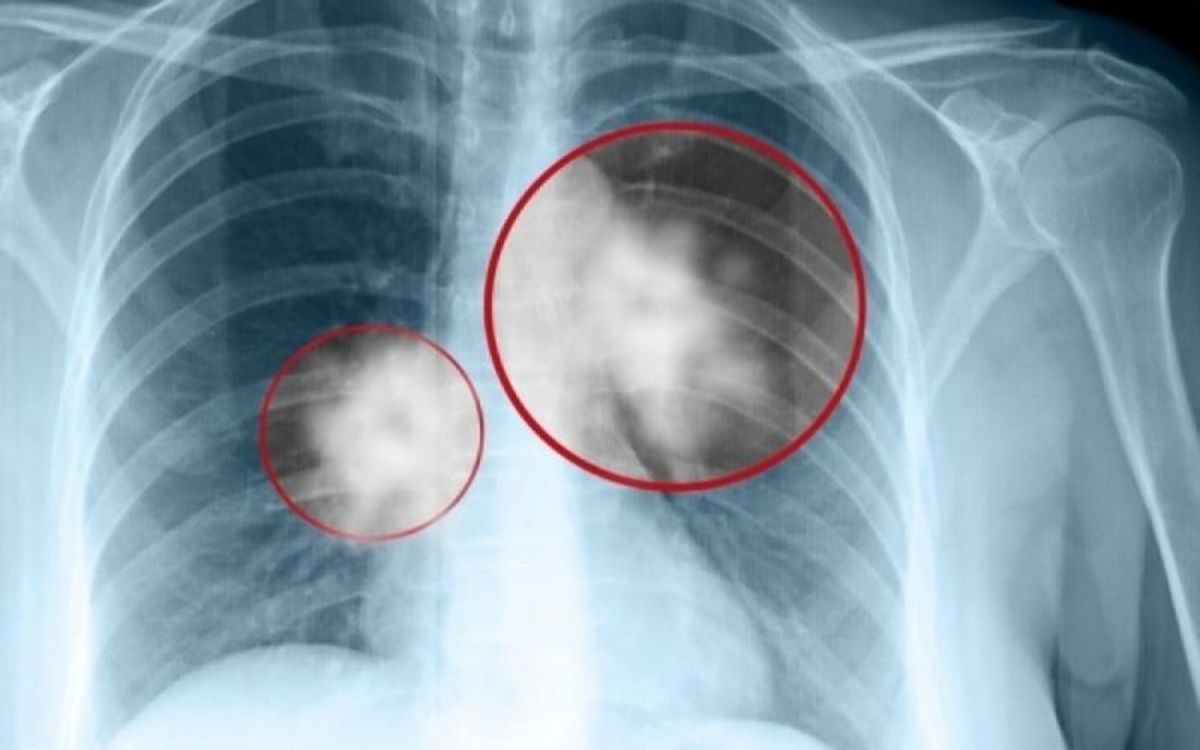

Για να πάμε ακόμη μακρύτερα, εάν σοκαριστείτε από την απαισιόδοξη διάγνωση του ογκολόγου, και αισθανθείτε μεγάλο φόβο θανάτου,

ο εγκέφαλός σας θα αρχίσει Καινούργιο Πρόγραμμα Παραγωγής Υπερκυττάρων Στον Πνεύμονα, που αργότερα θα χαρακτηριστεί από τους γιατρούς

σαν μεταστατικός καρκίνος του πνεύμονα.